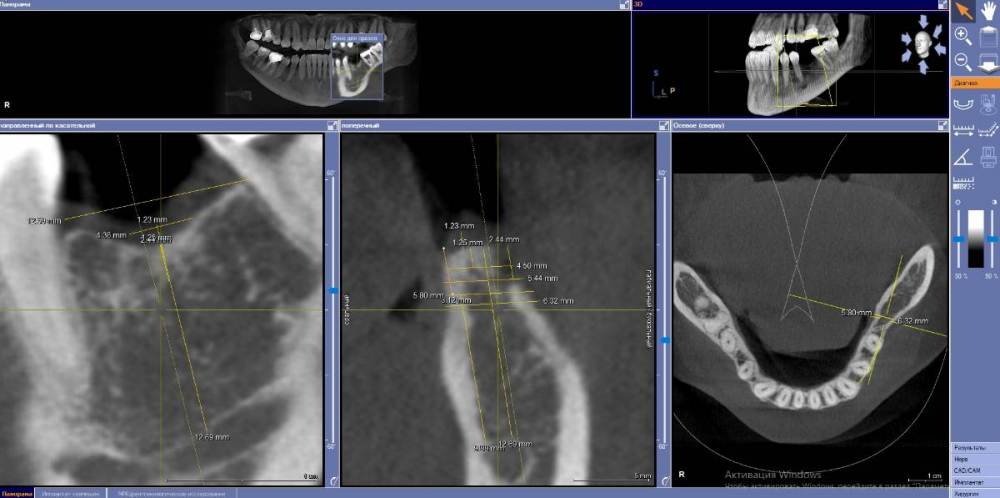

Fin Опубликовано 28 июня, 2021 Поделиться Опубликовано 28 июня, 2021 (изменено) Коллеги как бы Вы решили данную ситуацию? Давно хочу начать ставить поставить анкилос. Кто ставит как Вам клин ситуация для 3.5Х8 с заглублением в 3 мм? Пока склоняюсь к импланту диаметорм 4,5 заглубление (2 мм) и небольшой НКР спейсер+титановая сетка) потом работа с десной. Или все же поставить 4 на 8,5 +ССТ с заглублением 2,5 мм без НКР. Навигац шаблон во всех вариантах. Изменено 28 июня, 2021 пользователем Fin Ссылка на комментарий

Fin Опубликовано 28 июля, 2021 Автор Поделиться Опубликовано 28 июля, 2021 Подниму тему, немного пропал. Был в отпуске без интернета, а потом отходил от отпуска пару недель. 07.07.2021 в 23:53, АнтонТЛТ сказал: Я сотни 4.0 в моляры ставил и всё было хорошо, 3.5 тоже приходилось. Пока без проблем было. На оригинальной протетике переломов винта и имплантата у меня не встречалось. Что использовалось в данном случае, лучше спросить у Олега. В его клинике делалась работа в 16 году. Вы бы поставили 4ку в данном случае? 08.07.2021 в 21:26, Bier сказал: Сюда легко и 4.0 и 4.5 войдет. Надо выяснять. Но тут недозаглублен имплантат. ? Что делать, раньше так ставили. Я думаю, что в этом проблема. Лизис кости и затем перелом. В ширину 5.8 имплант 4.5. Вы имеете ввиду частично оголить вестибулярную часть импланта и поработать с десной? Ссылка на комментарий

Bier Опубликовано 30 июля, 2021 Поделиться Опубликовано 30 июля, 2021 28.07.2021 в 22:33, Fin сказал: В ширину 5.8 имплант 4.5. Вы имеете ввиду частично оголить вестибулярную часть импланта и поработать с десной? ну если ширина гребня 5.8 а диаметр препаровки ложа примерно 4.1-4.2 с чего вы взяли, что вестибулярная часть имплантата обнажится? Ссылка на комментарий

Fin Опубликовано 2 августа, 2021 Автор Поделиться Опубликовано 2 августа, 2021 (изменено) 30.07.2021 в 22:17, Bier сказал: ну если ширина гребня 5.8 а диаметр препаровки ложа примерно 4.1-4.2 с чего вы взяли, что вестибулярная часть имплантата обнажится? Благодарю за ответ. Все верно. Но если брать информацию того же Томаса Линчкевикуса он советует что бы минимум был 1 мм кости вокруг. Следовательно делаем 1 мм с язычной поверхности то с щечной поверхности будет около 0,3(грубо говоря нет). Изменено 2 августа, 2021 пользователем Fin Ссылка на комментарий